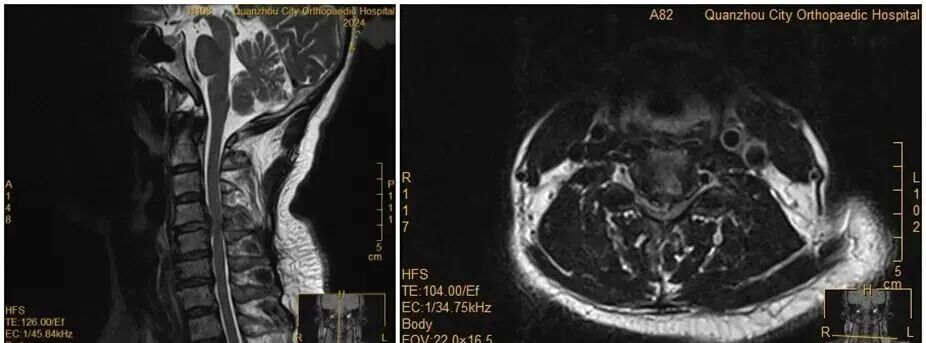

王女士術(shù)前MRI

沒(méi)想到,會(huì)診當(dāng)晚,王女士翻身拿手機(jī)的瞬間,雙手突然失去知覺(jué)——關(guān)鍵肌肌力降至1級(jí)或0級(jí),確診為癱瘓。“推測(cè)是翻身時(shí),脫出的椎間盤(pán)突然進(jìn)一步卡壓到脊髓神經(jīng),引發(fā)了急性癥狀?!贬t(yī)生表示。

雖然已經(jīng)出現(xiàn)了癱瘓,但王女士仍不愿意接受手術(shù)。經(jīng)過(guò)醫(yī)務(wù)團(tuán)隊(duì)及王女士家人耐心解釋及勸解后,王女士才愿意接受手術(shù)治療。手術(shù)后,經(jīng)過(guò)一段時(shí)間恢復(fù),她的肢體功能逐漸回歸正常。